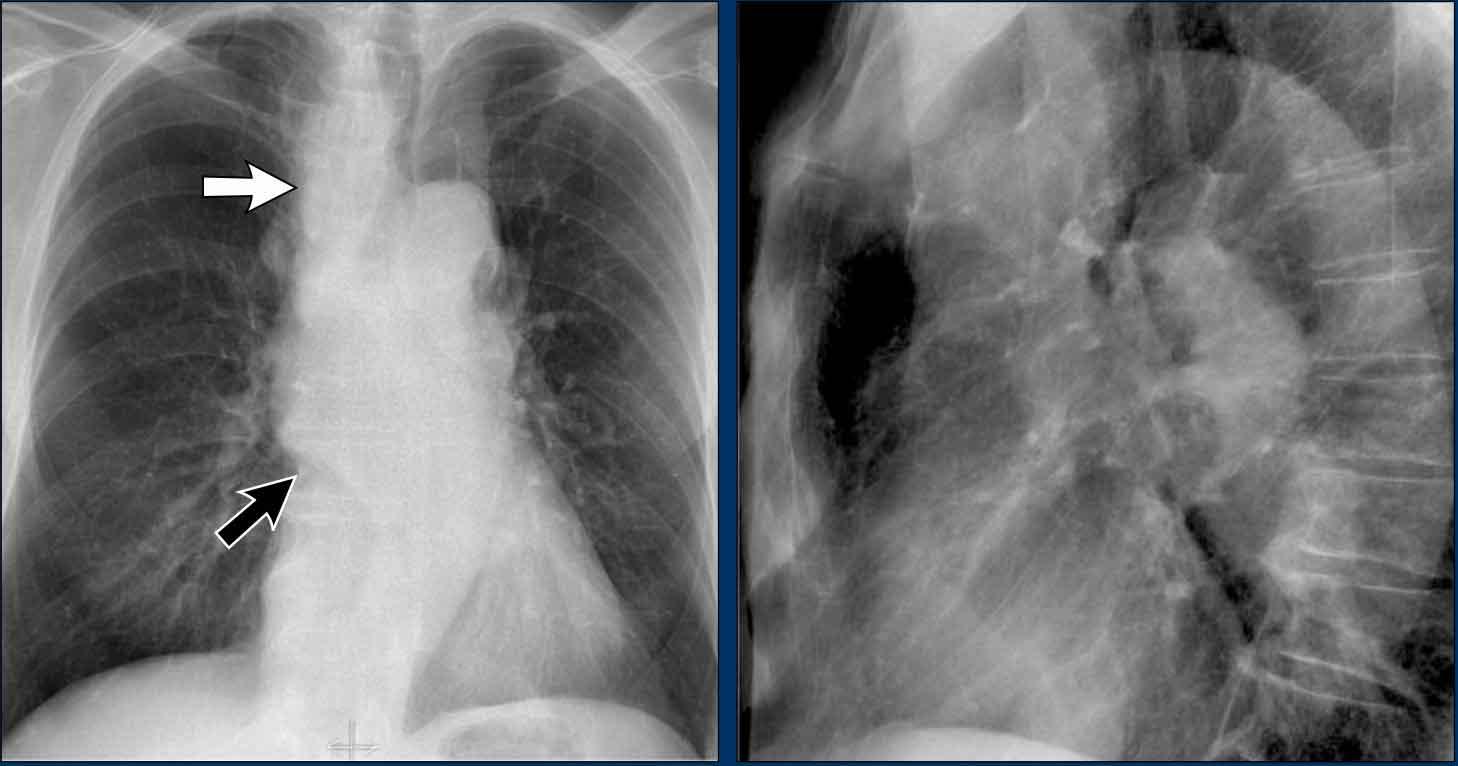

To rốn phổi – ca 1

Trong trường hợp này, bóng rốn phổi to ra ở cả hai bên. Nguyên nhân có thể do mạch máu giãn to hoặc hạch bạch huyết to. Một dấu hiệu rất có giá trị trong trường hợp này là khối nằm bên phải khí quản.

Đây được gọi là dấu hiệu 1-2-3 trong bệnh sarcoidosis, tức là to rốn phổi trái, rốn phổi phải và hạch cạnh khí quản.

Dưới đây là thêm một số ví dụ về bệnh sarcoidosis.

Nhấp vào hình để phóng to.

- Hạch bạch huyết to và hình ảnh kính mờ (ground-glass) ở phổi

- Hạch bạch huyết to, dấu hiệu 1-2-3

- Hạch bạch huyết to khối lớn

- Dấu hiệu 1-2-3

- Hình ảnh nốt ở phổi, không có hạch bạch huyết to

- Hạch bạch huyết rốn phổi và cạnh khí quản to

Dịch chuyển đường azygô-thực quản (2) – Hạch to dưới carina

Một nguyên nhân thường gặp gây dịch chuyển đường azygô-thực quản là hạch to dưới carina (trạm 7).

Trên phim X-quang ngực, lưu ý hình ảnh đường azygô-thực quản bị đẩy lên trên ngay dưới carina, phù hợp với hình ảnh hạch bạch huyết dưới carina to (mũi tên đen).

Ngoài ra còn thấy hạch to cạnh khí quản phải, đẩy dải cạnh khí quản phải (mũi tên trắng) và làm lệch khí quản sang trái.

Tiếp tục với hình ảnh PET-CT…

Hình ảnh PET

- PET-CT cho thấy hình ảnh hạch to tăng chuyển hóa lan rộng ở trung thất và vùng cổ, rõ ràng hơn so với trên phim X-quang ngực.

- Các hạch bạch huyết vùng cổ có liên quan — đây là phát hiện quan trọng vì chúng có thể tiếp cận được để sinh thiết.

Tiếp tục với hình ảnh CT và siêu âm…